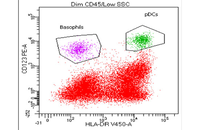

- Cell isolation based on surface markers by MACS method

- Evaluation of cell apoptosis by flow cytometry

- Evaluation of cellular oxidative stress by flow cytometry